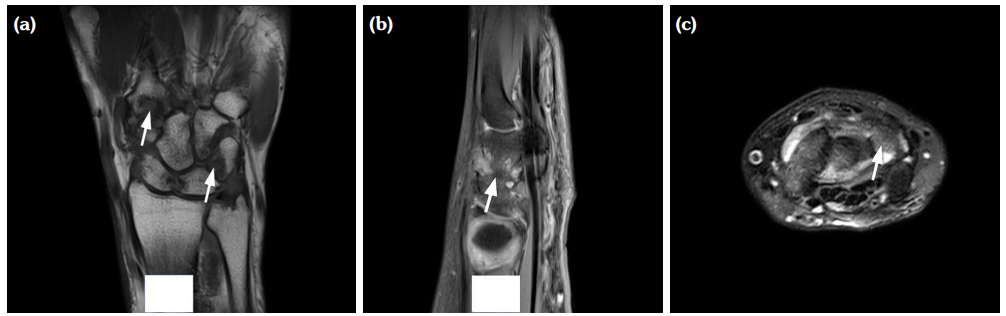

The degree of BE and synovial hyperplasia in SNRA or SPRA is more serious, and the blood flow signal is more abundant. However, the degree of synovial hyperplasia in osteoarthritis was mild, and no obvious blood flow signal was detected (Figures 1, 2, 3 and 4). Magnetic resonance imaging (MRI) studies of SPRA also showed serious BE (Figure 5).

Among SNRA, SPRA and non-RA, there was no significant difference in the grades of SH, PD, BE, nor the number of cases of tendinitis and tenosynovitis between the SNRA group and the SPRA group (p>0.05) (Table 3). There were, however, statistically significant differences in the number of cases of SH1, SH3, PD and BE grades between the SNRA and non-RA groups (p<0.001). There was no significant difference in the number of cases of SH2, PD2, tendinitis or tenosynovitis between the SNRA and non-RA groups (p>0.05) (Table 4).

Our findings suggest that the use of synovial blood flow and the degree of BE are helpful in distinguishing RA from non-RA, which may be explained by the underlying pathological changes. The pathological features of RA include primary synovial inflammation, which produces aggressive synovial pannus attached to the cartilage, causing hypoxia and erosion of the bone. Synovitis caused by non-RA disease is mostly due to inflammation, edema and thickening of synovium due to degenerative or pathological changes of cartilage and cortical bone. It is not difficult to understand that the invasive synovial blood vessels during RA are closely related to the phenomenon of BE; thus, the combination of the two ultrasonic characteristics are sound pathological indicators for the evaluation of RA.